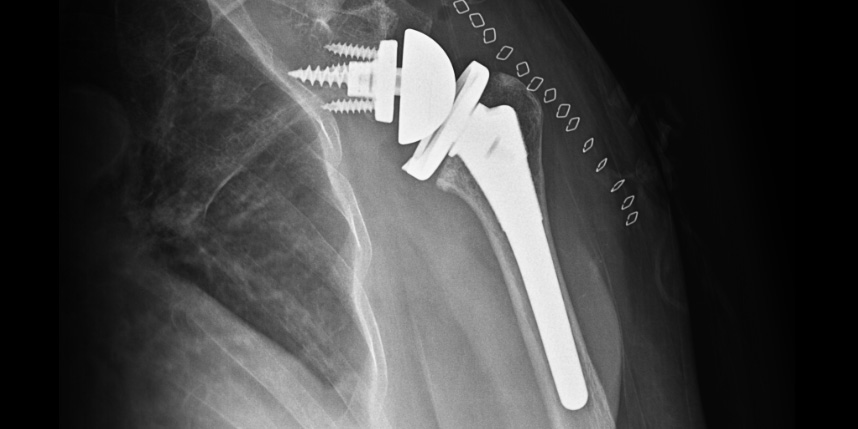

삼하게 망가져 거의 기능이 없는 관절을 제거한 후 특수하게 제작된 인공관절을 삽입하는 수술

비수술 치료에도 호전이 없는 경도의 관절염에서 시행합니다.

역행성 인공관절 전치환술

역행성 인공관절 진치환술

(회전근개 심한 파열 및 관절염 진행)